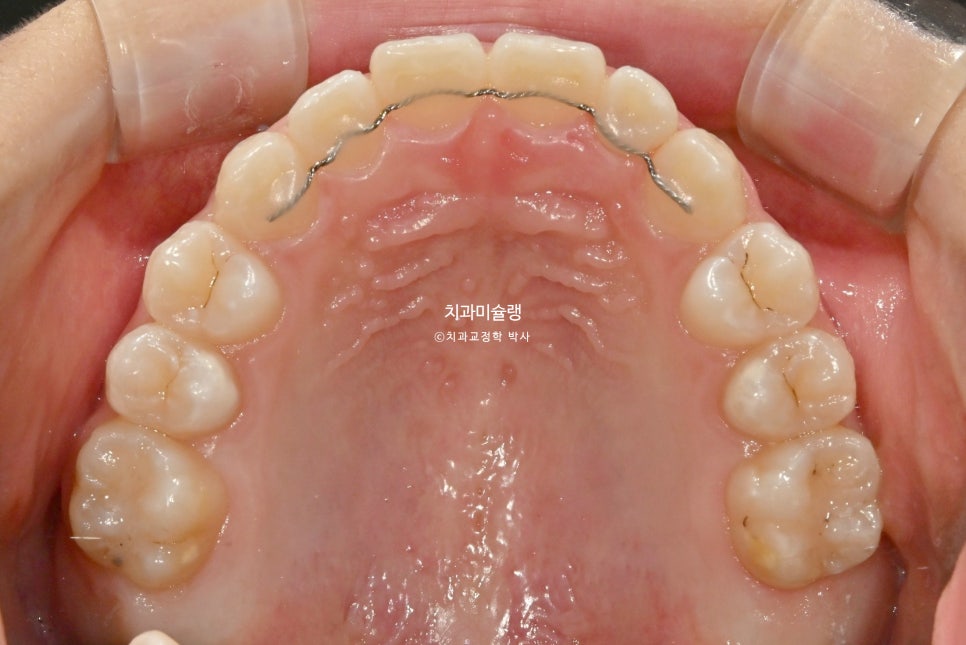

2026년 2월 – 치료 완료

2026년 2월, 정상교합이 달성되어 치료를 마무리 합니다.

중심선은 잘 맞으며 절단교합으로 인항 개방교합은 해소되었습니다.

어금니 교합관계는 1급을 달성.

3급 교합관계를 1급으로 만들기 위해 치료기간 내내 3급 고무줄을 사용했습니다.

결과가 성인교정치료 결과에 준한만큼 유지장치도 성인과 동일하게 들어갑니다.